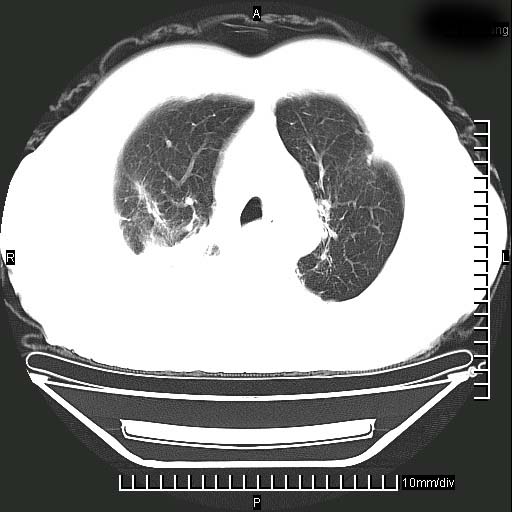

标题: CT24043:胸部增强:男性,60岁

既往肺结核,近10几天,咳嗽,咳痰,右侧胸痛,疼痛较明显,右上肺斑块考虑结核灶胸膜粘连,增强,可惜动脉期没有定好,未见强化,可延迟4分后又见较明显强化,中心见低密度影,如果说结核是边缘强化,可这个灶强化的面积挺大的,让人很挠头。

1)两肺继发性肺结核。2)右侧胸膜增厚+少量胸腔积液。